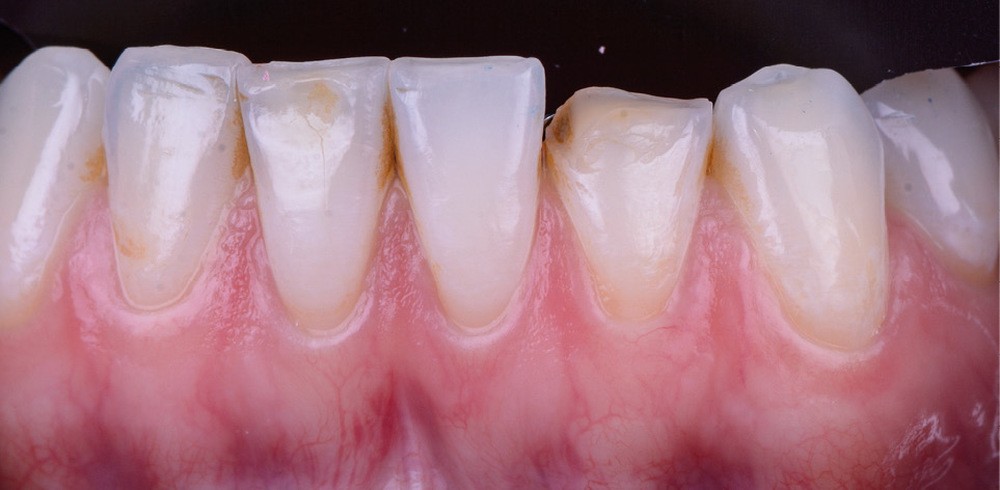

Il existe aujourd’hui sur le marché des résines composites fluides chargées, résistantes mécaniquement et qui présentent de bonnes propriétés optiques. Le choix d’une résine qui présente de bonnes propriétés optiques impose néanmoins une photopolymérisation en fine épaisseur. Ainsi, dans le cas d’une perte de substance supérieure à 2 mm, il est préférable de reconstruire la surface en plusieurs incréments [2]. L’injection de résine au travers de la clé ne concerne ainsi que la couche la plus superficielle.

Afin d’obtenir un comportement optique le plus proche possible de celui de la dent naturelle, l’auteur recommande de réaliser le corps de la dent au préalable à l’aide d’un composite de restauration plus saturé. C’est uniquement la couche la plus superficielle qui est injectée. La technique d’injection de composite nécessite le respect d’un protocole strict et comporte quelques difficultés qu’il convient d’anticiper.